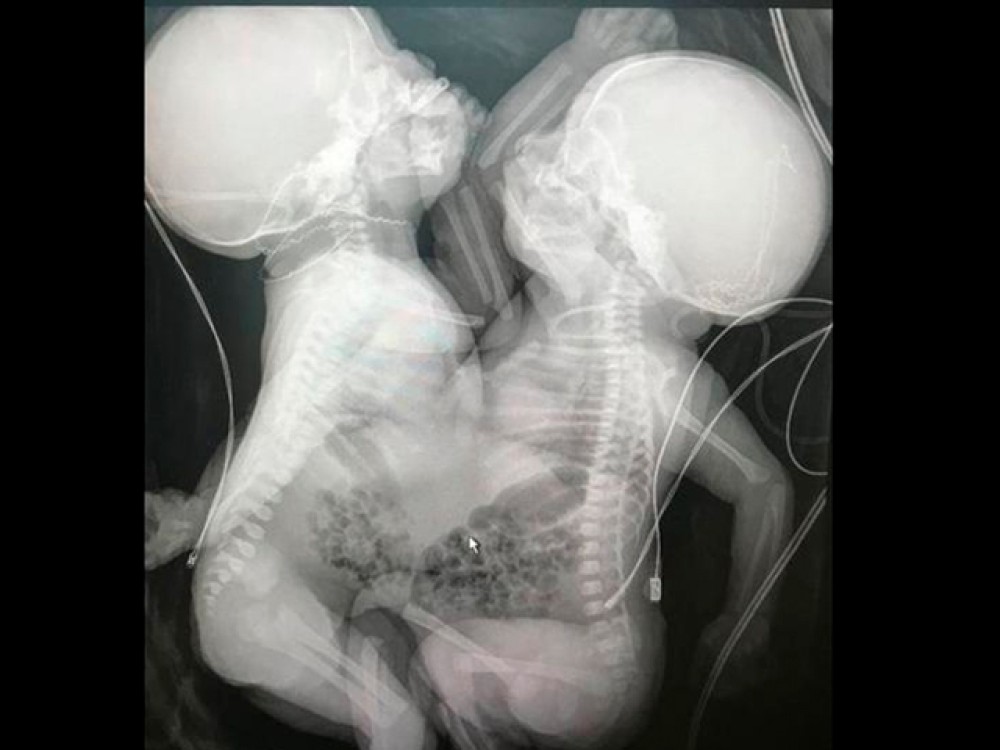

Decisão do TJ/SP reformou sentença inicial e determinou que o Estado realizasse o procedimento com urgência após constatar risco à gestante e ausência total de vida extrauterina.